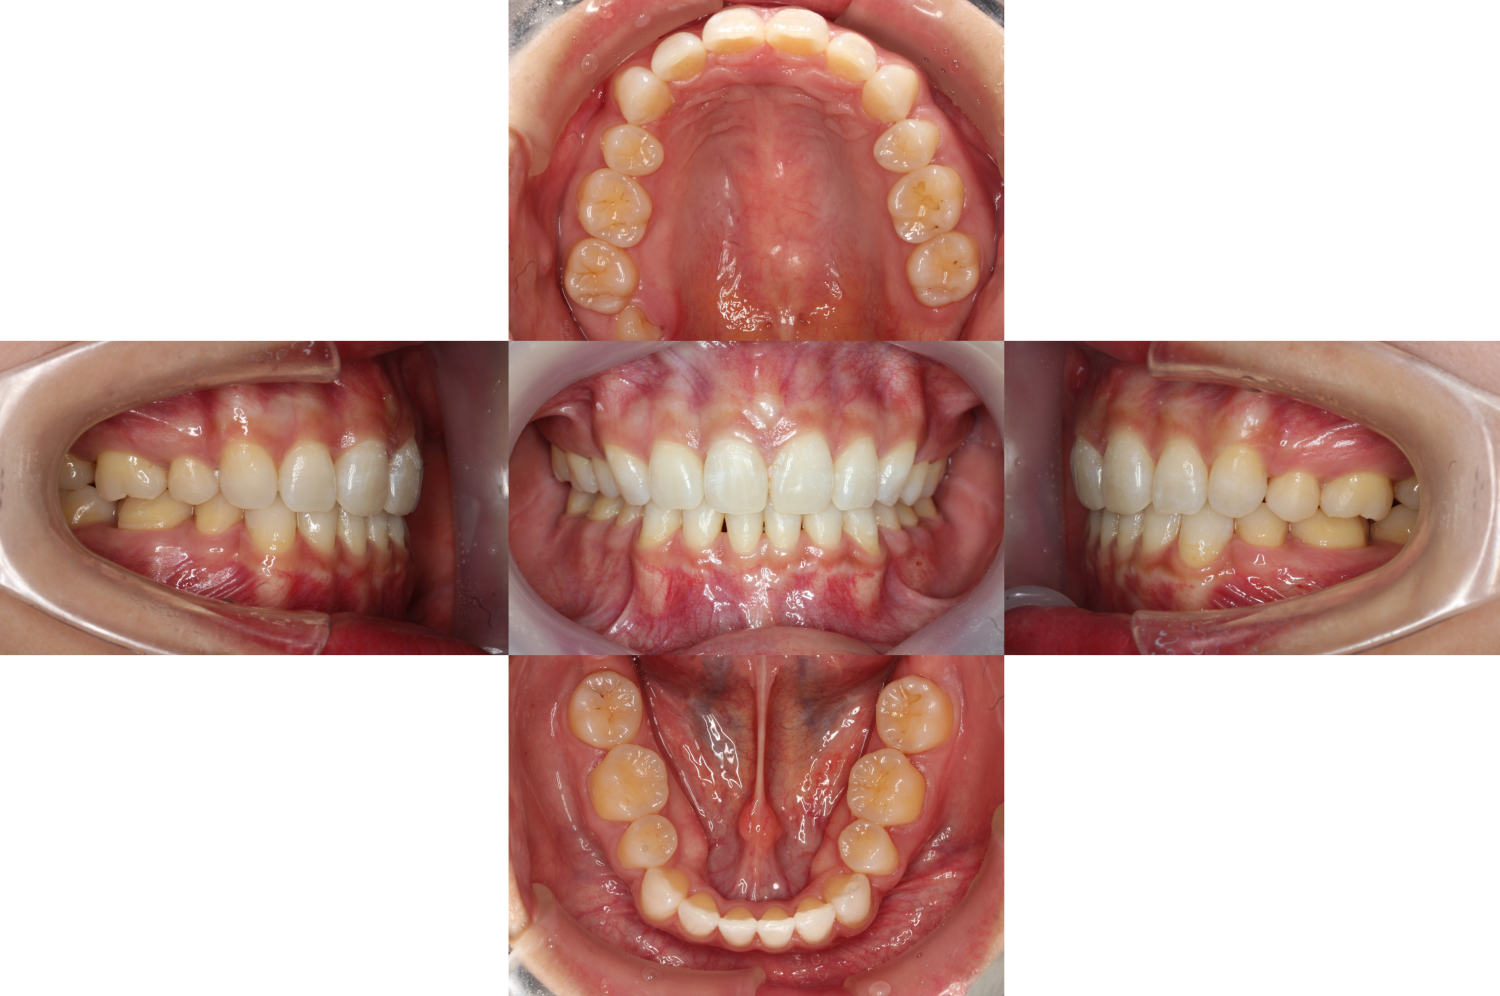

【口元を下げたい】お悩みが改善し

上下の歯もしっかり噛んでいます。

右上の奥には親知らずが生えてきたので

綺麗な歯並びを維持するために抜歯を検討しています。